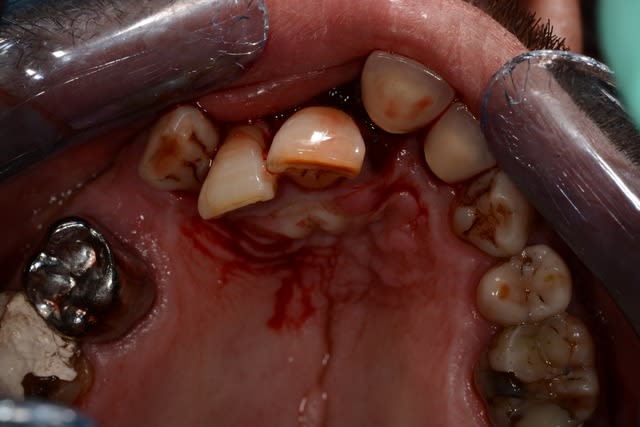

Ne jamais provoquer quelqu'un qui tient un marteau dans sa main !

La lèvre doit être dans un bel état.

La carrosserie doit avoir morflé aussi ! Non ?